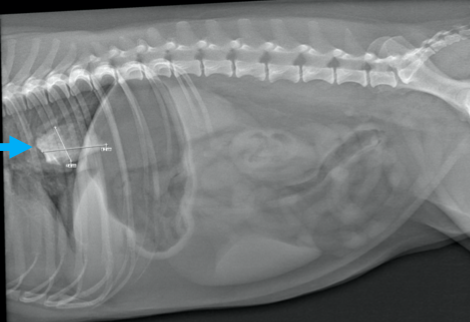

Quelle est l’opacité du CÉ retrouvé dans l’oesophage?

minérale

Quel est votre conclusion radiographique? Énumérez quelques diagnostics différentiels.

=> masse splénique

Ddx : néoplasme, granulome, kyste, hématome, nodule hyperplasique